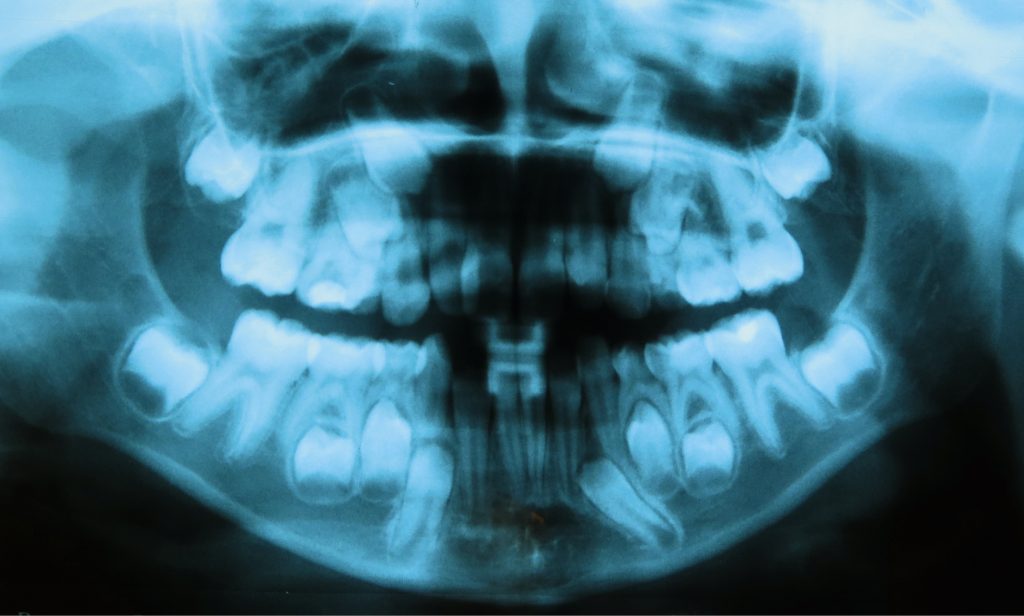

Opóźniony rozwój zębów 15 i 25 – przegląd piśmiennictwa i obserwacje własne

Streszczenie: Diagnostyka i postępowanie lecznicze w przypadku anomalii zębów to ważny obszar ortodoncji i stomatologii dziecięcej. Większość anomalii zębowych ujawnia się w dzieciństwie i wiele z nich jest nieprawidłowo diagnozowanych lub pozostaje nieleczonych z powodu braku doświadczenia lub postrzegania ich jako „za trudne” przypadki [22]. Planowanie leczenia powinno być interdyscyplinarne. Wyrzynanie się zębów jest złożonym procesem, na który wpływ ma bardzo wiele czynników. Znaczne odchylenia od ustalonych norm dla czasu wyrzynania zębów powinny mobilizować lekarza do ustalenia powodu opóźnionego rozwoju zębów [1]. Delayed tooth eruption (DTE) może wynikać z lokalnych zaburzeń lub być manifestacją choroby systemowej [1]. Wymiana zębów mlecznych na stałe może być zaburzona w związku z nietypową budową zębów przedtrzonowych drugich, ich opóźnionego rozwoju lub braku rozwoju [2].